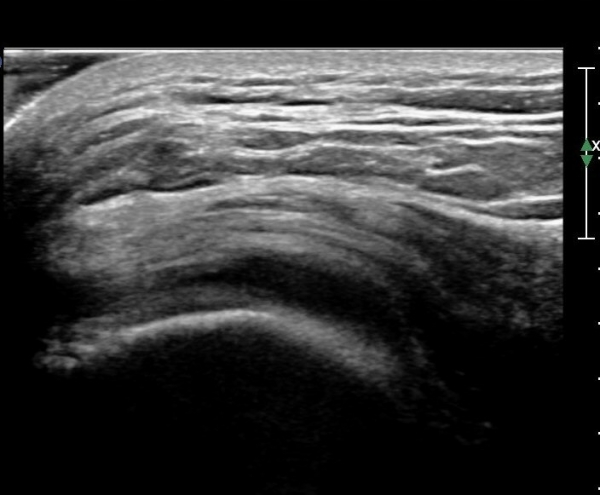

ŽÃËÀÚ¸¦ ¸Ó¸®ÂÊÀ¸·Î À̵¿ÇÏ´Ï ¼ö¾×Àú·ù°¡ ´õ ¸¹ÀÌ °üÂûµÈ´Ù(»çÁø 2, 3).